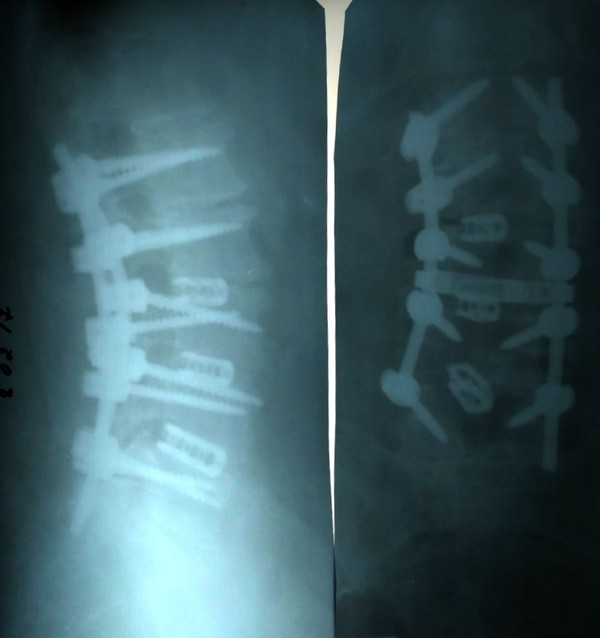

Андрей Анатольевич показал рентген, сделанный больным после операции при многоуровневом стенозе (сужении позвоночного канала). Пациента сопровождали постоянные болевые ощущения, приходилось ежедневно принимать специальные обезболивающие препараты, которые к тому же не приносили особого эффекта. В результате была проведена соответствующая операция, которая имеет такое сложное название: многоуровневая декомпрессия позвоночного канала, транспедикулярная и межтеловая стабилизация позвоночника на уровне от L1 (от 1-го поясничного) до S1 (до 1-го крестцового позвонка).